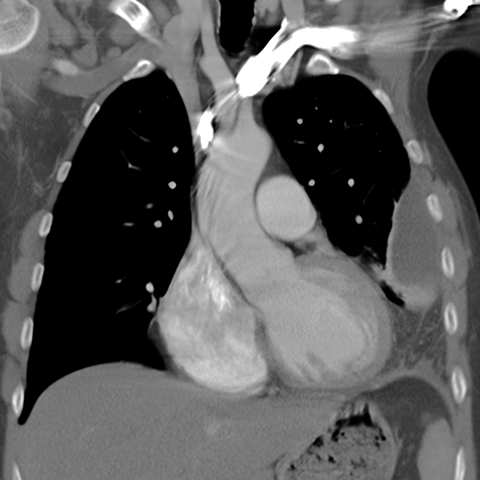

Large, Loculated Pleural Effusion [2 of 3]